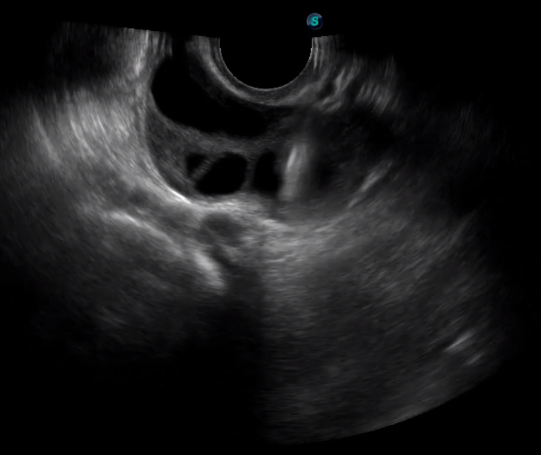

1生殖專用探頭

傳統(tǒng)腔內(nèi)探頭采用直柄設(shè)計(jì),在搭配穿刺架使用時(shí),手術(shù)空間小,不易操作;生殖專用的曲柄探頭,探頭柄采用彎曲成角度設(shè)計(jì),可實(shí)現(xiàn)監(jiān)視、取卵兩不誤,搭載穿刺架時(shí),可以清晰顯示穿刺針的進(jìn)針過(guò)程、深度和位置,實(shí)時(shí)監(jiān)視取卵全過(guò)程,保障取卵操作精準(zhǔn)與安全。

取卵臨床圖